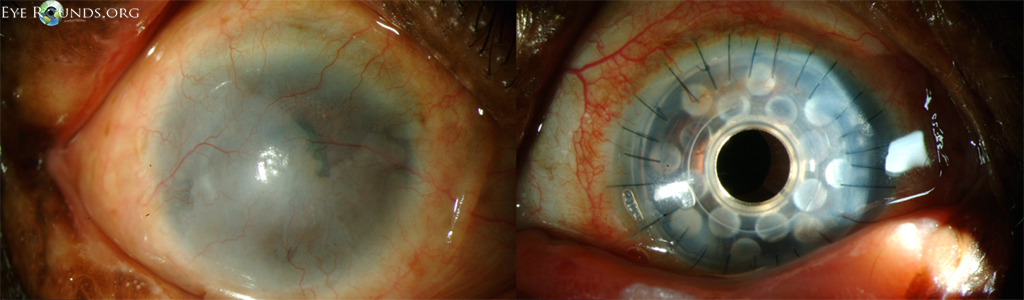

PK is a full-thickness transplant procedure, in which a trephine of an appropriate diameter is used to make a full-thickness resection of the patient's cornea, followed by placement of a full-thickness donor corneal graft. Interrupted and/or running sutures are placed in radial fashion at equal tension to minimize post-operative astigmatism (Figure 2). Later, the sutures are removed selectively to reduce the amount of astigmatism present. A transplant can last decades with proper care (Figure 3). While once the most prominent type of corneal transplant, PK has been supplanted by partial thickness techniques for endothelial dysfunction without significant stromal scarring. PKs are performed primarily for visually significant stromal scarring, opacities with an uncertain status of the endothelium or significant posterior corneal involvement, corneal ectasia (such as keratoconus and pellucid marginal degeneration, especially if there is history of hydrops), combined stromal and epithelial disease (such as Peters anomaly), and infectious or non-infectious corneal ulcerations or perforations (1, 14). A variant of the procedure, the mini-PK, can be used to treat more focal defects in the cornea (Figure 4).